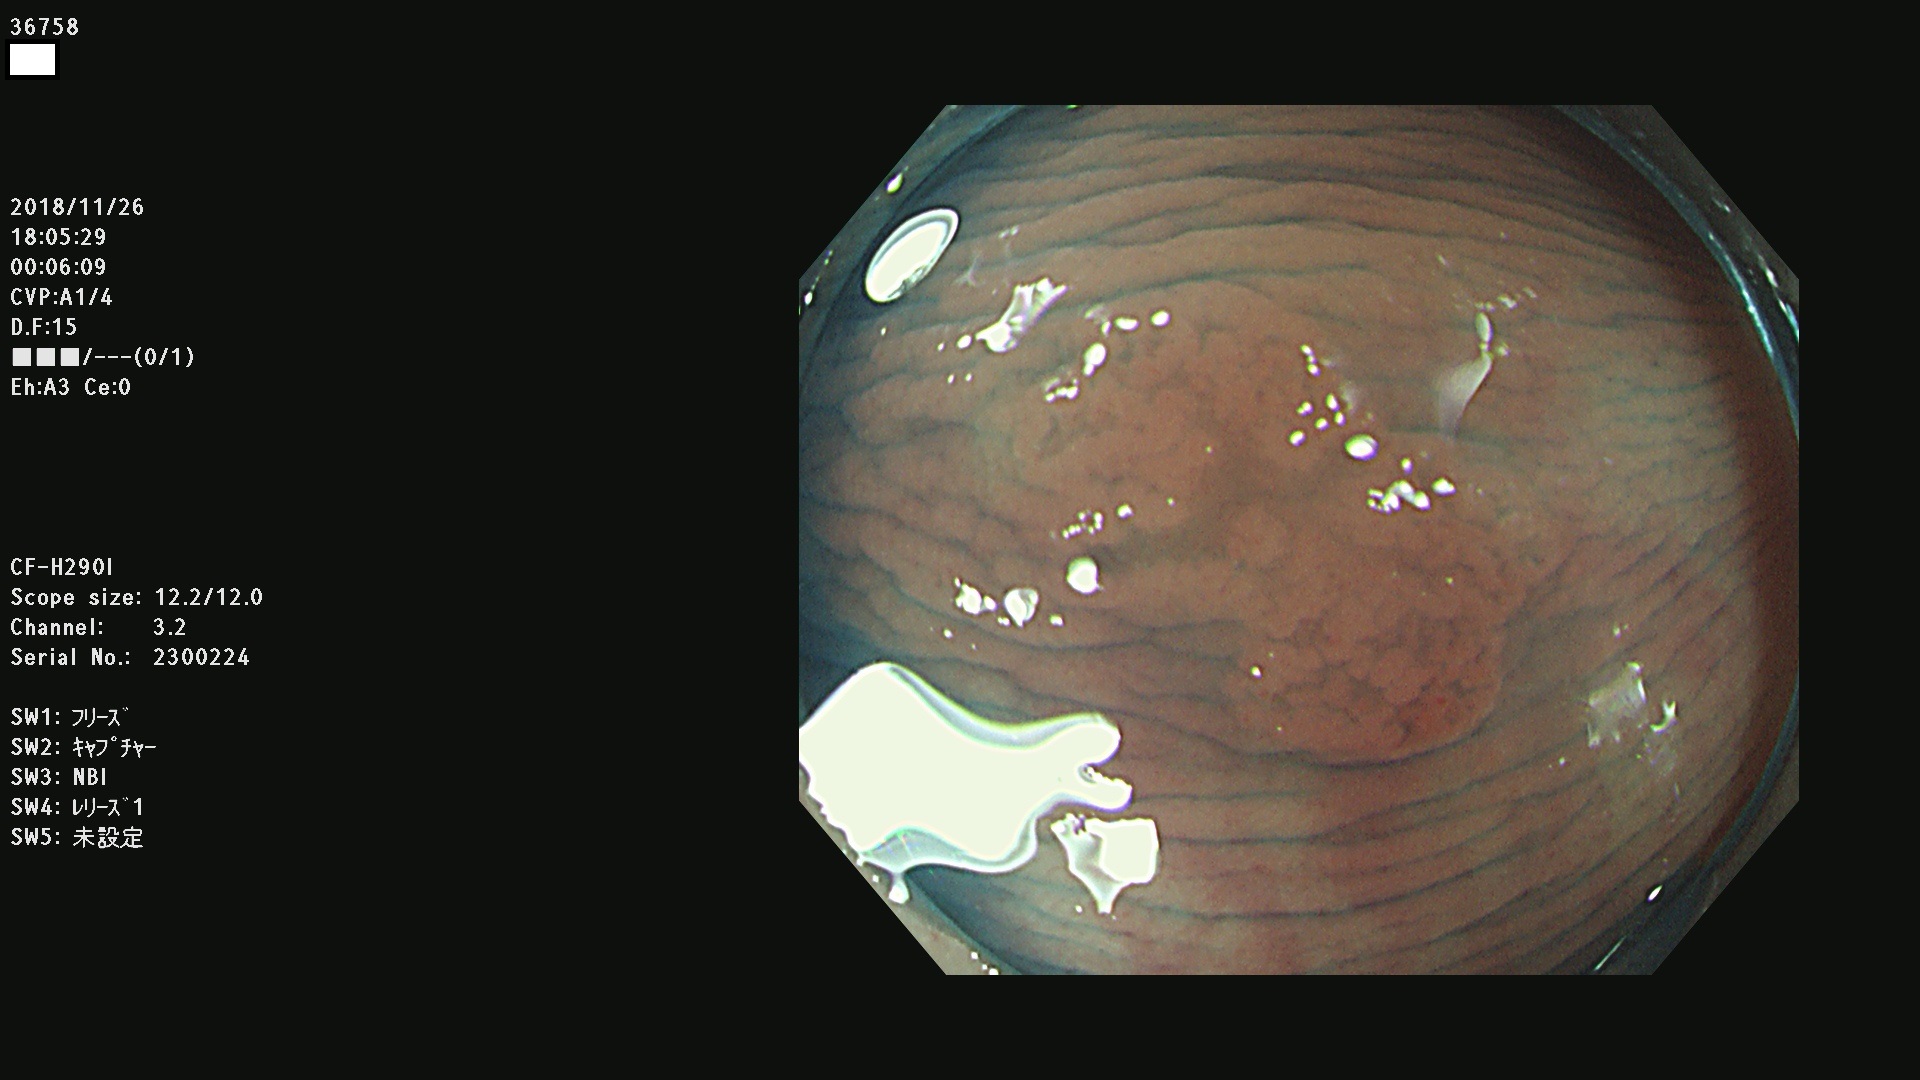

36700 36701 36702 36704 36705 36707 36708 36710 36712(SSAPのみ) 36714 36715 36716 36717 36718 36721 36723 36724 36730 36731 36732 36734 36735 36736 36738 36739 36742 36744 36745 36746 36749 36752(SSAPのみ) 36754 36756 36758 36759 36760 36731 36732 36734 36737 36738 36739 36771(SSAPのみ) 36772 36773 36774 36775 36776 36777 36780 36781 36783 36785 36786 36788 36790 36792 36794 36797 36798

発見困難で危険性の高い平坦型病変(上記100名より抽出)